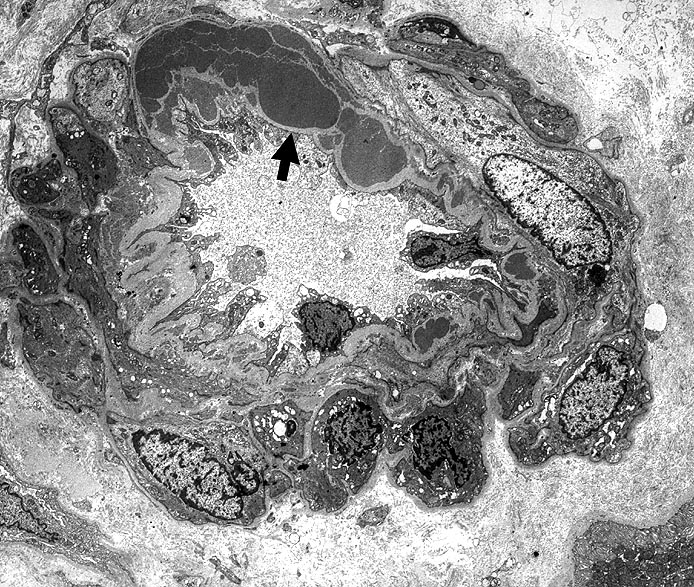

Arteriolosklerose bei Diabetes Frühstadium

Innerhalb der Basalmembran gelegene plumpe Proteinablagerungen. Die glatten Muskelzellen sind in der gesamten Peripherie erhalten.

Typisch für Diabetes mellitus ist der Befall von Vas afferens und efferens, oft auch der Vasa recta. In intrarenalen Arterien unspezifische Atherosklerose teilweise mit Atheromen (typisch für Diabetes). Der Schweregrad korreliert im allgemeinen mit dem Ausmass der exsudativen Läsionen der Glomerulosklerose. Die Arteriolosklerose im Vas afferens beim Diabetes ist identisch mit der Arteriolosklerose bei arterieller Hypertonie.